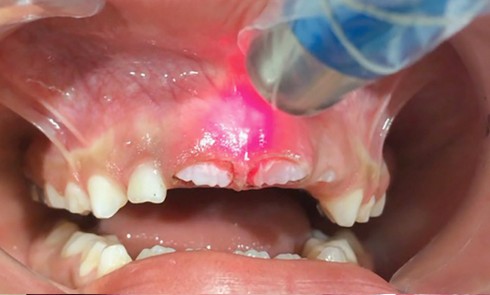

Grand Prix éditorial 2024 – Laser au quotidien 1er cas lauréat 2024 Examen clinique Il révèle des lésions d’ostéochimionécrose (OCN)...Intégration du laser diode dans la pratique orthodontique

Grand Prix éditorial 2024 – Laser au quotidien 2e cas lauréat 2024 L’examen clinique et radiologique (fig. 1) a mis...